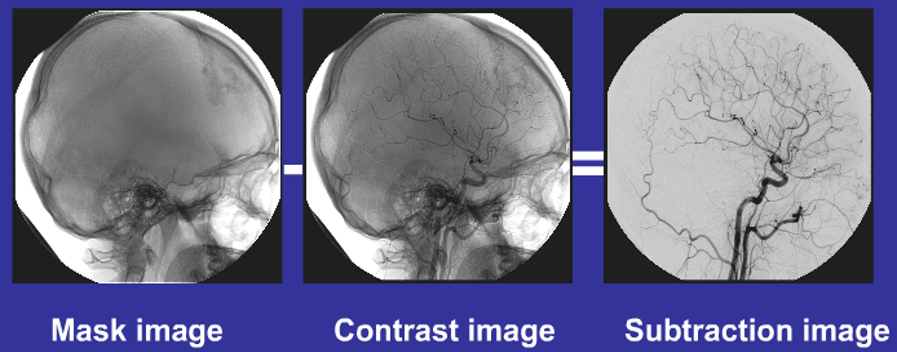

3、DSA